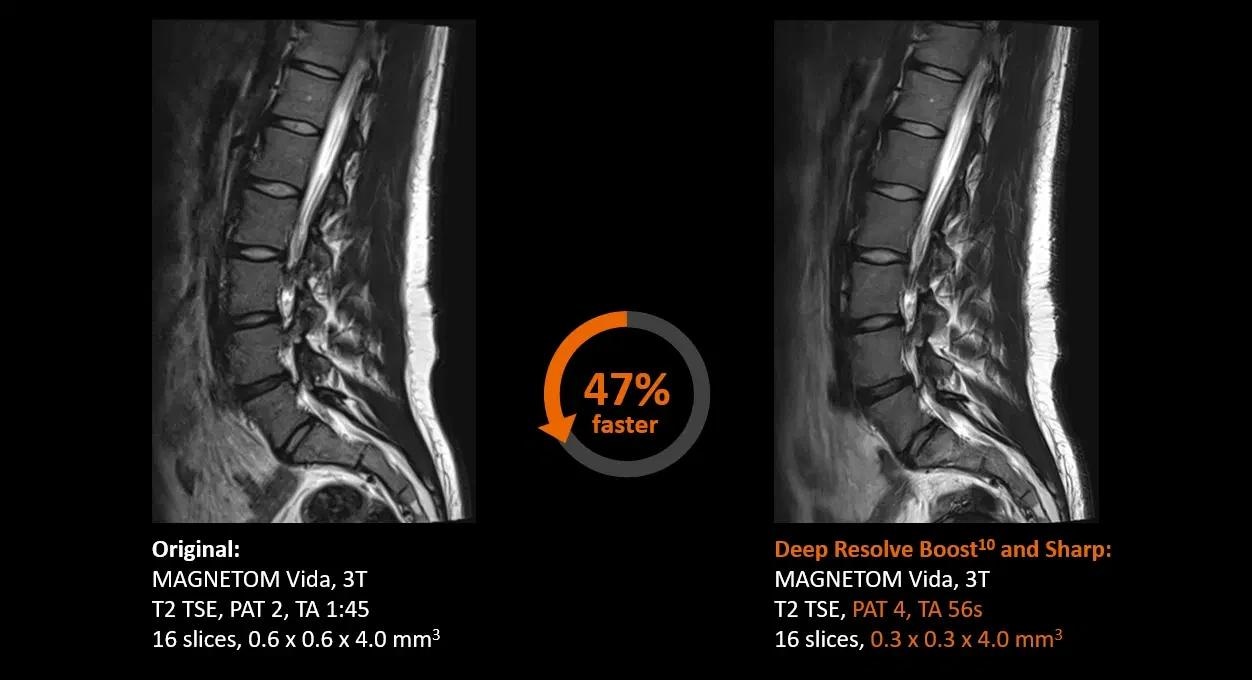

Deep Resolve5

Sharper images at a faster rate than ever before.

Deep Resolve—Faster than ever before

Deep Resolve is an AI-powered image reconstruction system that uses convolutional neural networks to expedite MR scans, making them faster than ever before. Faster scans increase workflow efficiency while boosting patient satisfaction.

Deep Resolve’s raw data-to-image reconstruction and extremely quick acquisition are game changers in MRI, allowing for the generation of actionable insights that can be diagnostically useful. In a secure digital environment, an open interface is intended to foster cooperation and co-creation. Deep Resolve technology is one step closer to creating a healthy world for all.

Spine

Image Credit: Siemens Healthineers